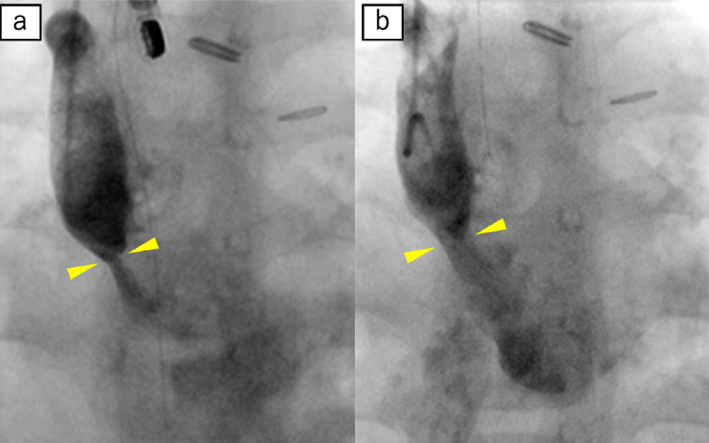

入院後経過(Fig. 4)

便中α1-アンチトリプシンクリアランスの測定や99mTc消化管シンチグラフィーは未実施であったが,低アルブミン血症と下痢などの臨床症状,および他疾患の除外から,PLEと診断した4).入院と同時に,内科的治療の強化として脂肪制限食を導入し,静注利尿剤を併用した.入院3日目の心臓カテーテル検査ではSVC baffle内に最小径2.2 mmの狭窄を認め,5 mmHgの圧較差を伴い,SVC圧は10 mmHgと上昇していた(Fig. 5).IVC baffleに狭窄は認めず,IVC圧は7 mmHgと正常であった.SVC狭窄に対し経皮的血管形成術を施行し,最小径5.0 mm,圧較差1 mmHgに改善した.なお12 mm径のバルーンカテーテルによる拡張中に体血圧が低下し,拡張中の経胸壁超音波検査でSVC baffleに隣接する肺静脈還流路の閉塞を認めた.患者の年齢・体格も考慮し,ステント留置は見送られた.同治療後に静注薬を終了し入院11日目に退院した.前後して各症状は軽快し,発症1か月後の血清Alb値は4.5 mg/dLまで改善し,脂肪制限を解除した.その後2年間PLEの再燃なく経過している.

Pediatric Cardiology and Cardiac Surgery 39(1): 9-15 (2023)

Fig. 5 Superior vena cava angiograms

(a) There is a discrete stenosis in the superior caval pathway. (b) The stenosis is improved by balloon dilatation.